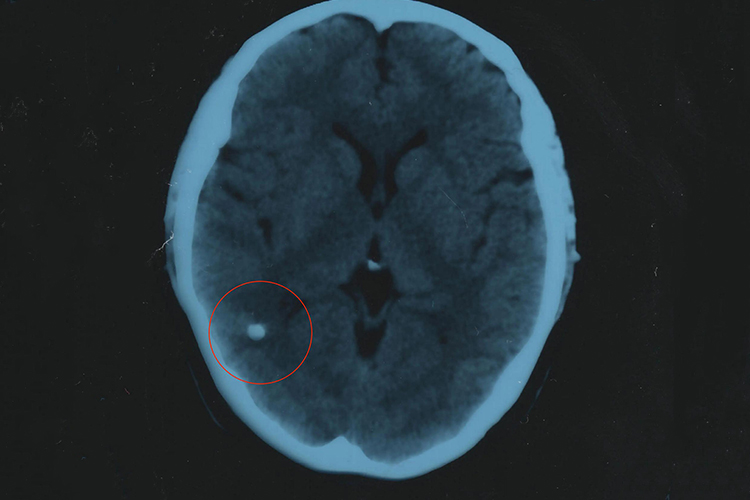

脑瘤是生长于颅腔内的肿瘤,良性脑瘤包膜完整,生长慢,恶性脑瘤无包膜,生长迅速,可出现颅内压增高和神经功能异常等症状。

脑瘤是生长于颅腔内的肿瘤,可分为良性和恶性。良性脑瘤生长缓慢,包膜较完整,不浸润,周围组织及分化良好。恶性脑瘤生长较快,无包膜,界限不明显,呈浸润性生长,分化不良。

脑瘤无论良性或恶性,均能挤压、推移正常脑组织,造成颅内压升高和神经功能异常。临床上主要表现为头痛、呕吐、肌力减退、癫痫等症状。